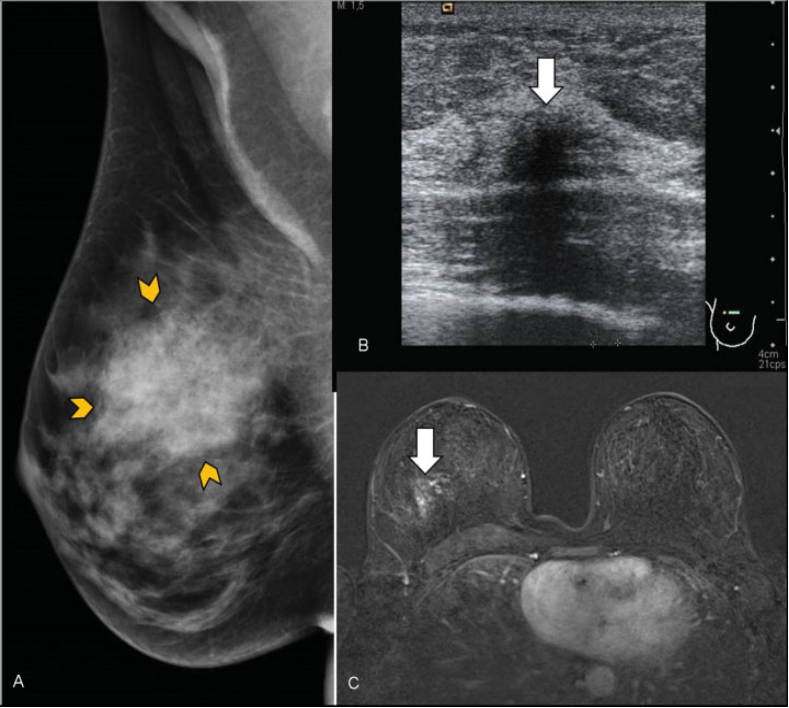

Neoplasia lobulillar in situ. Mujer de 48 años que acudió por masa palpable en mama derecha. (A) Mamografía digital mama derecha. Aumento de densidad de morfología nodular en cuadrantes superiores (delimitado por puntas de flechas amarillas). (B) Ecografía. Nódulo hipoecoico de morfología irregular y bordes mal delimitados (flecha). (C) RM con contraste intravenoso. Se apreció un realce asimétrico, no masa, con distribución focal (flecha). Se realizó BAG con control ecográfico con resultado de neoplasia lobulillar in situ. Al realizar cirugía de la lesión completa, se obtuvo el mismo resultado.